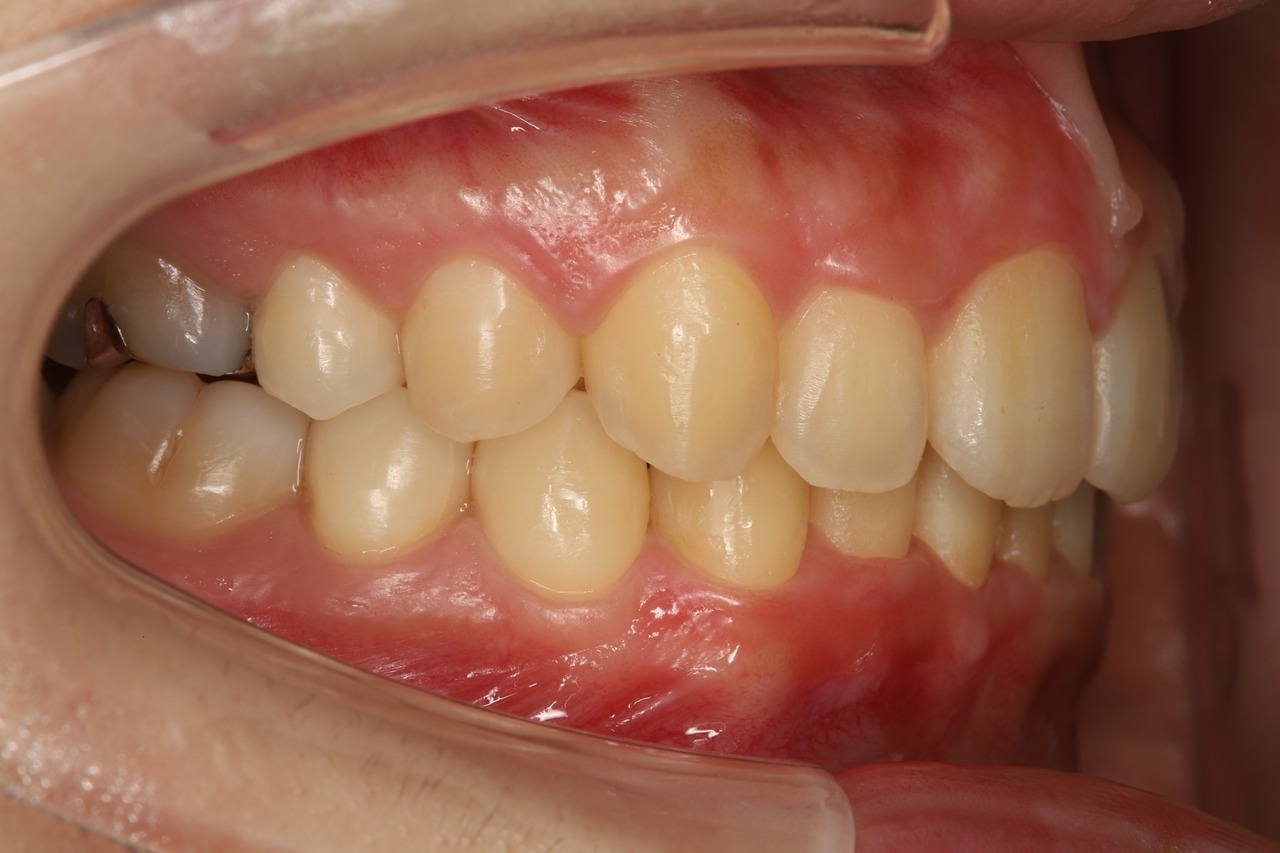

当院でのインビザライン治療例

こちらは当院でマウスピース矯正を行った患者さまです。前歯だけでなく奥歯の咬み合わせまで含めて調整することで、将来的な歯の健康や歯並びの安定を守ります。

Before

After

出っ歯が治り、歯と歯の間に隙間もありません。

奥歯がしっかりと噛み合い、安定した咬み合わせになっています。